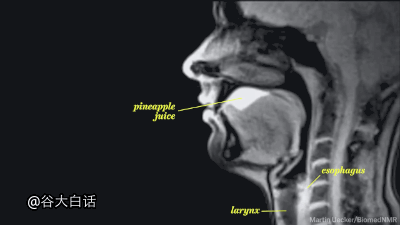

#爱你爱到骨头里#【MRI下诡异而奇妙的人体】这是一段用核磁共振成像技术制作的动态短片,将人类喝水、亲嘴、嘿咻、拉翔、生娃、说中文、说德文等日常活动展现得毫纤毕现、一览无遗。doge微猎奇,微暴,慎点。